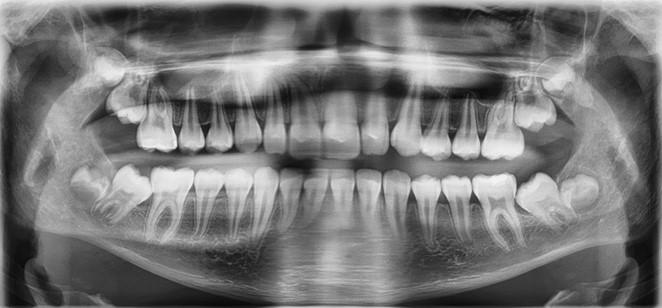

A healthy 12-year-7-month-old female, with an adult dentition, presented with a chief complaint of “teeth not coming in straight,” as was identified to her and her parents by a referring dentist. On clinical examination, the patient had pleasing facial esthetics on an orthognathic skeletal base. Intraorally, the patient had Angle Class I molar relationship bilaterally with well-aligned arches but impacted mandibular second molars with partially visible crowns (Figure 1). The panoramic radiograph confirmed the mesioangular impactions of the mandibular second molars bilaterally along with the third molars at the early crown calcification stage of development (Figure 1). An increase in inclination of second molars can be seen bilaterally, on examination of panoramic radiographs at ages of 10 years and 5 months and 11 years 10 months, which were 17 months apart (Figures 1 and 2).

Fig. 1: Initial presentation of mesioangular impacted mandibular second molars at 10 years and 5 months of age. Note that the mandibular third molars are at about a third crown completion stage of development.only for the understanding purpose.

Fig. 2: Follow-up radiograph at the age of 11 years and 10 months, 17 months after the initial detection of the mandibular second molar impactions. Note that the mesioangular inclinations of both molars had worsened with the further crown development of the mandibular third molar crowns and their positions translating superiorly.

Fig. 3: Seven-month post-surgical removal of developing third molars showing spontaneous improvement in the angulation of the left mandibular second molar at 12 years and 7 months of age. The right mandibular second molar showed little change.

Fig. 4: Post orthodontic uprighting of the mandibular second molars at 14 years and 10 months.

Fig. 5a: Age: 12 years, 7 months

Fig. 5b: Age: 17 years 7 months